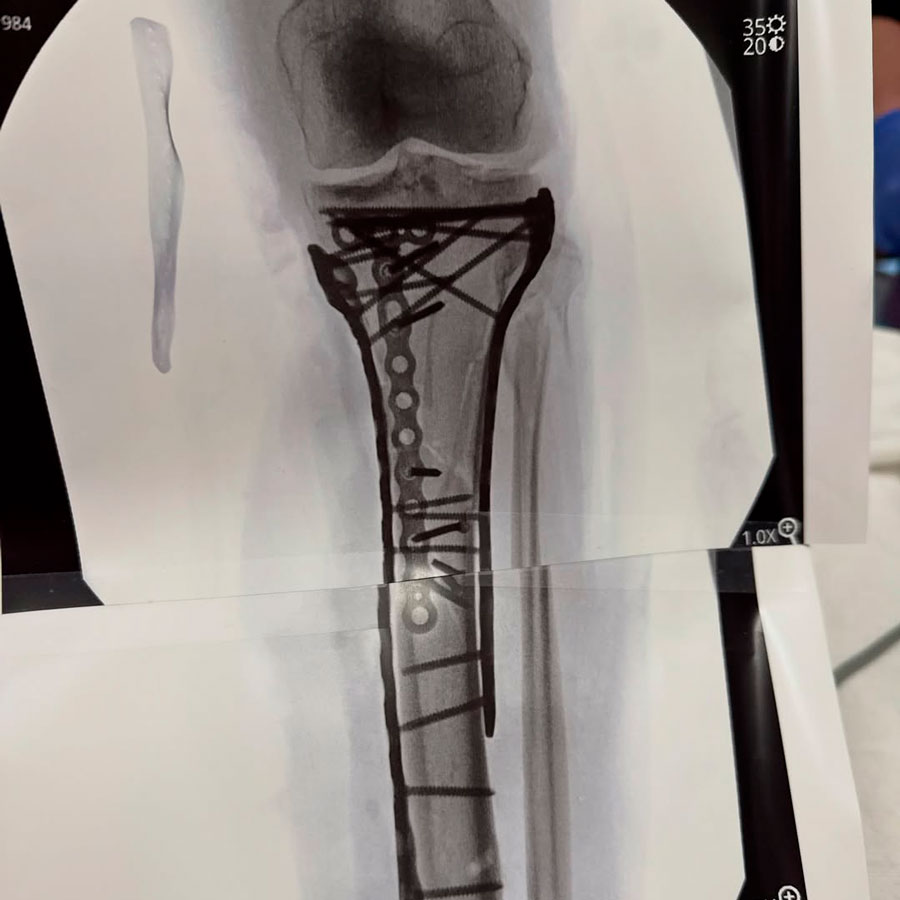

"У меня сложный перелом большеберцовой кости и перелом головки малоберцовой кости – там все разлетелось на части. А осложнилось тем, что развился компартмент-синдром", – рассказала она в своих социальных сетях.

"Так что доктор, Том Хэккет, спас мою ногу. Спас от ампутации. Он провел фасциотомию: разрезал левую ногу с двух сторон, чтобы дать ей «дышать»", – отметила она.